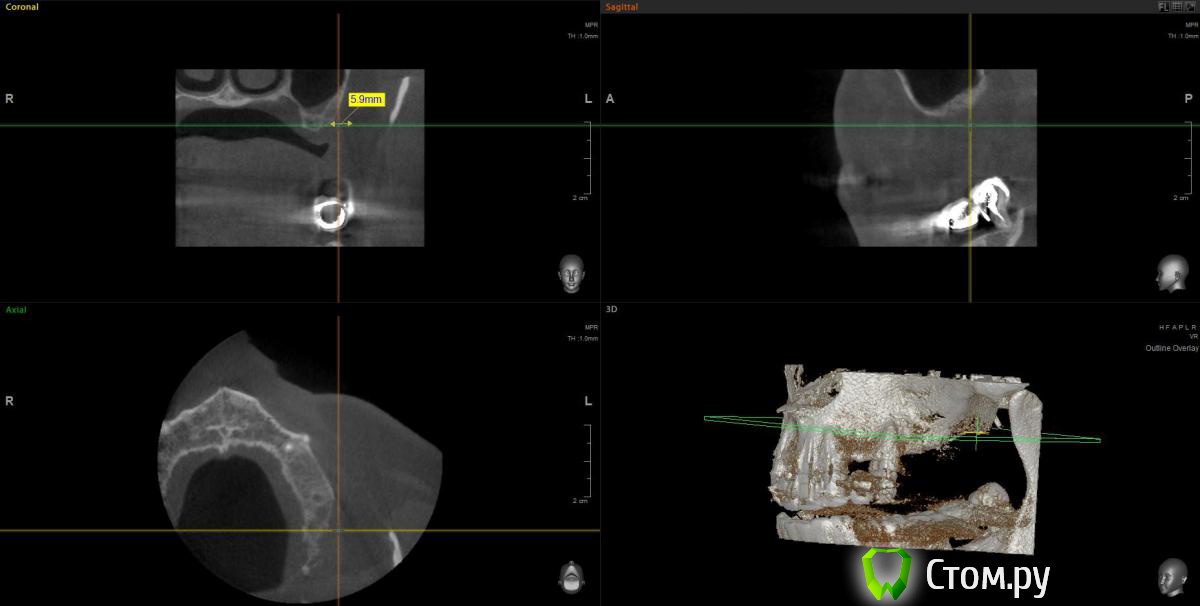

wladdX Опубликовано 11 февраля, 2014 Поделиться Опубликовано 11 февраля, 2014 (изменено) Прошу прощения за вторжение в чужую тему (администратор, поправьте), но ситуация похожа. Т.е. помимо синус-лифтинга надо увеличить ширину альвеолярного отростка. Предполагаю поступить примерно, как продемонстрировал Mane выше. Но может подойдёт "метод полужёстких каркасов? Кстати септа в пазухе замысловатая. По поводу остальных сегментов и прочих проблем - пациент на них не настроен, интересует его только зона 25,26,27 Изменено 11 февраля, 2014 пользователем wladdX Ссылка на комментарий

Sahan Опубликовано 11 февраля, 2014 Поделиться Опубликовано 11 февраля, 2014 Ну для планирования такой работы при КТ во рту должен был быть хирургический шаблон. А так никаких проблем. Открытый синус , плюс имплантаты , плюс сетка. Ссылка на комментарий

wladdX Опубликовано 12 февраля, 2014 Поделиться Опубликовано 12 февраля, 2014 Да, отсутствие шаблона при КТ, недочёт Хотя wax-up то сделан, недоработка, будем исправляться.По поводу сетки как-то не подумал даже, вероятно, потому что пока не пользовался. Возникает вопрос - для НКР под сеткой не слишком протяжённый дефект? Опасаюсь как-то в данной ситуации сразу имплантировать, первичной стабильности, скорее всего, не получить. Хотя сама по себе идея мне очень нравится: менее травматично и технически проще. Вот и чешу репу Ссылка на комментарий